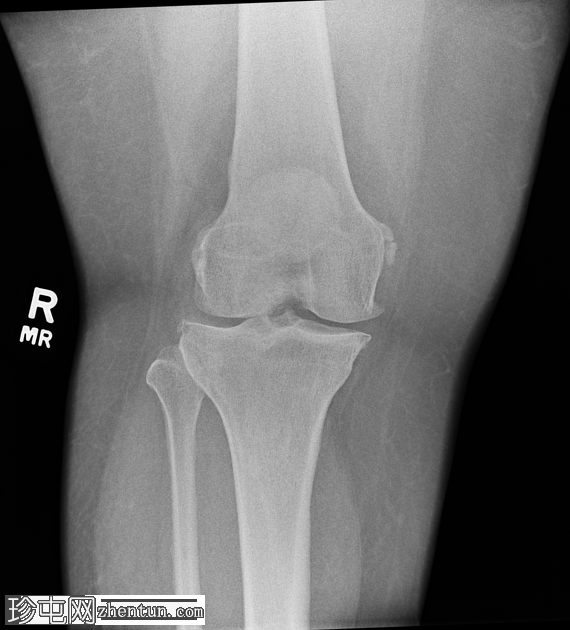

正位片

右膝中度骨关节炎(3级),表现为内侧胫股关节和髌股关节间隙狭窄,边缘可见骨赘、髌骨骨刺和胫骨棘突。

内侧副韧带近端附着处股骨内侧髁附近可见长圆形软组织骨化,提示为佩莱格里尼-斯蒂达(Pellegrini-Stieda)损伤。

病例讨论

膝关节周围钙化的一个常见部位是内侧副韧带近端附着处的钙化,称为佩莱格里尼-斯蒂达(Pellegrini-Stieda)损伤,这反映了膝关节旧伤累及内侧副韧带并伴有营养不良性钙化。